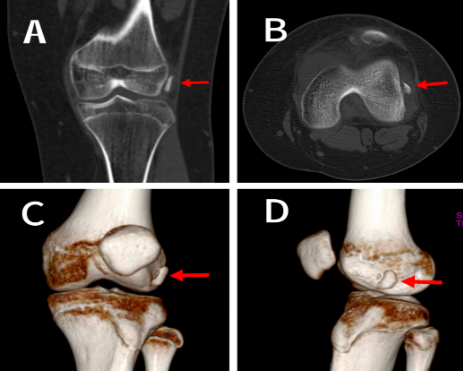

术前CT检查示:图A~D:髌骨骨折后,骨折片游离于膝关节外侧隐窝(红色箭头所示)